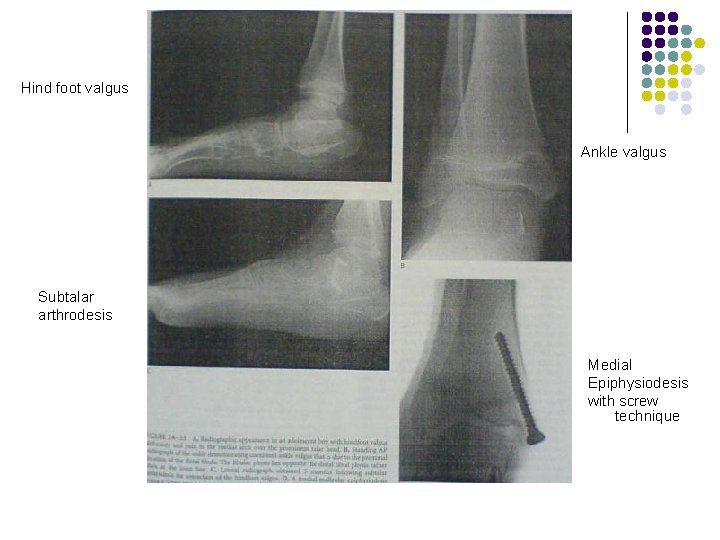

Hind foot valgus Ankle valgus Subtalar arthrodesis Medial Epiphysiodesis with screw technique

Ankle valgus Valgus alignment of the ankle develops in patients with neuromuscular diseases. Radiographs of ankle in standing should be obtained before surgical correction of Pes valgus. v v v I. II. v v Surgical correction is done by. . Hemiepiphysiodesis of the distal medial tibia (medial screw, staples or open epiphysiodesis) Osteotomy is useful when immediate correction is desired. A Closing wedge osteotomy of distal tibia, combined with distal fibular osteotomy is performed.

Pes valgus Ø Ø Occurs in up to 25% of patients with cerebral palsy. and most common in older diplegic or quadriplegic patients. Can be caused by spastic peroneal muscles, weakness of the p. tibialis and a tight gastrocsoleus. Radiographs should be obtained in standing position for the foot and ankle. Conservative treatment should vigorously pursued. . shoe inserts and orthoses may be adequate to relive pain and avoiding surgery.